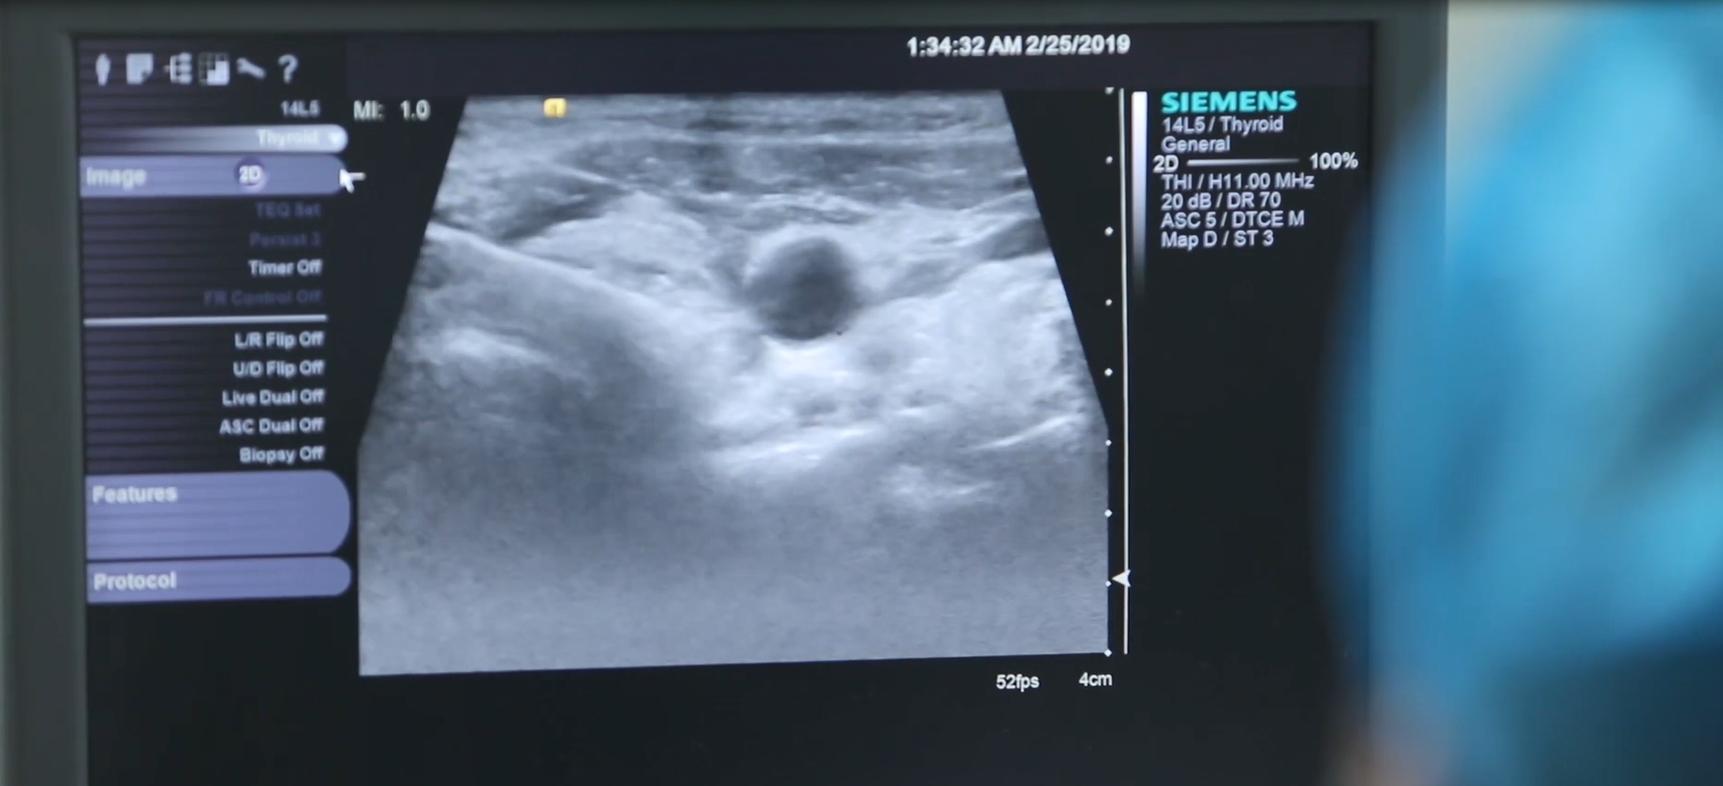

我当时看到倪女士肿着全身走进诊室,一眼就看出倪女士的情况比较严重了,检查完立刻安排她住了院。

检查后发现,倪女士的白细胞、白蛋白数目在危急值,也就是说,不管她吃什么,营养都吸收不了,只有赶紧降低指标,不然将会非常危险。

心电图检查报告显示倪女士有心脏衰竭,因为甲亢引起的心衰、心包积液,造成了倪女士的循环系统受损,因此导致倪女士全身肿胀,根本不能平卧。

时隔五年,倪女士的甲功报告出来,指标已经特别异常了,几乎所有的指标远高出或远低于正常值。

肚子肿胀,摸起来硬邦邦的,腿部脚部水肿,指压长时间无法回弹,脖子肿着……想到这些问题竟然都是因为小小的一个甲状腺器官导致的,倪女士感到难以置信。